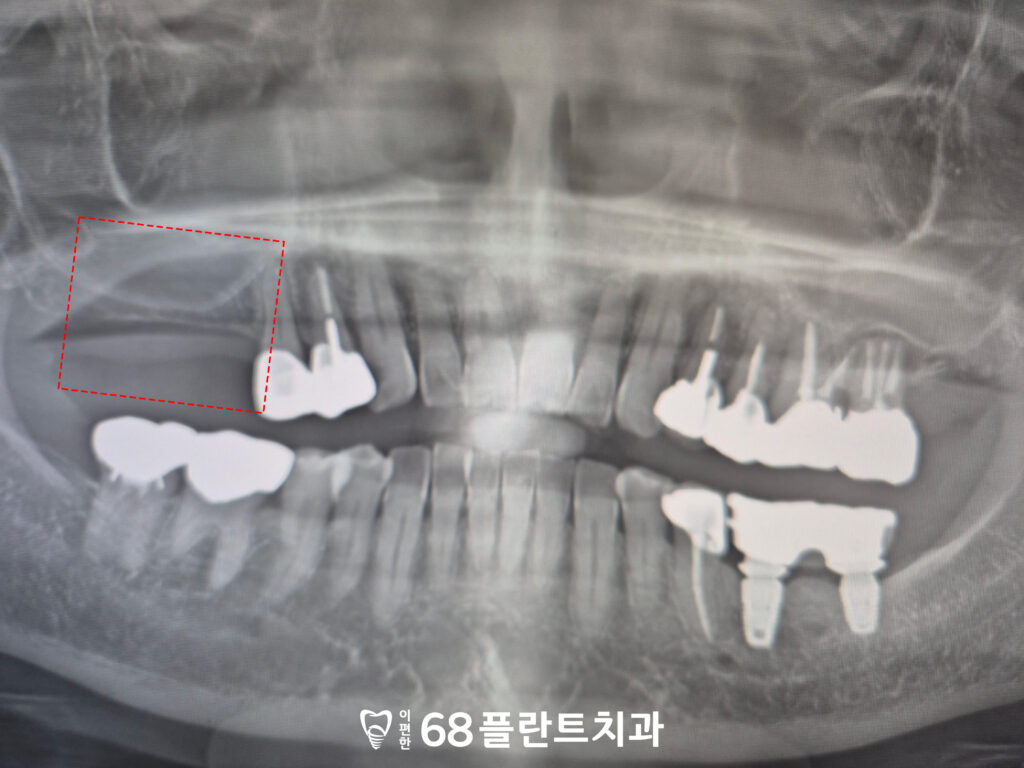

위 환자분은

오른쪽 위 치아의 상실로 인해

왼쪽으로만 식사를 하니 불편하여

철산역치과 이편한68플란트에

내원해 주셨습니다.

확인해 보니,

저작하는 데에 제일 도움이 되는

큰 어금니가 상실되어 있었습니다.

그래서 식사할 때 양쪽으로

골고루 씹기 힘든 상태였는데요.

또한 상실된 지 오래되어

잇몸뼈의 흡수가 진행되어,

임플란트를 안정적으로 식립하기 위한

충분한 뼈의 두께와 높이가

부족한 상태였습니다.